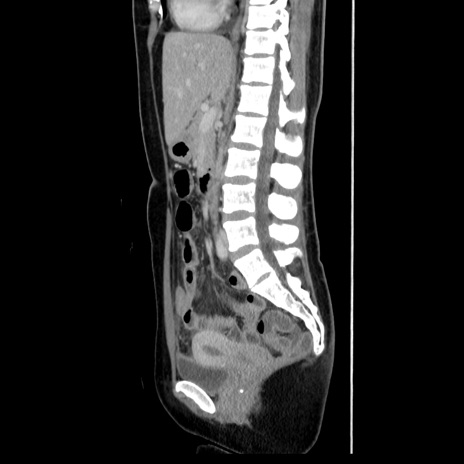

症例39(矢状断像)

【症例】40歳代女性

【主訴】上下腹部痛

【現病歴】2日目から下腹部痛あり。夜間は痛みで眠れなかった。昨日より上腹部痛と下痢が出現。臥位で痛みは軽快したため、休んでいた。本日になって臥位でも立位でも痛みが強くなってきたため救急要請。

【既往歴】子宮内膜症

【身体所見】部:平坦・軟、左上下腹部に圧痛あり、反跳痛あり。

【データ】WBC 21800、CRP 26.78

CT